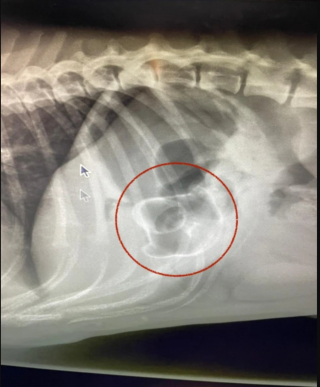

Lorsqu’ils sont arrivés à la clinique Pride Veterinary Center, Ronnie a été endormi par le vétérinaire Debs Smith, lequel craignait que l'objet coincé dans le corps du toutou lui provoque une obstruction des voies respiratoires. Il a effectué une radiographie, qu’il encadrera plus tard dans les locaux du centre.

Sur les images, le canard de bain apparaissait de manière très nette ! C’était une situation complètement insolite. Tandis qu’il pensait devoir opérer l’animal, Debs a finalement pu extirper le joujou à mains nues, à l’aide d’une caméra spécialisée. Au bout de 30 minutes, Ronnie a enfin été débarrassé de son (gros) morceau de plastique et il est rentré le jour même à la maison.

En plus des photos de la radiographie, l’équipe vétérinaire a souhaité conserver le fameux jouet, en souvenir de cette intervention cocasse, qui s’est finalement bien terminée.